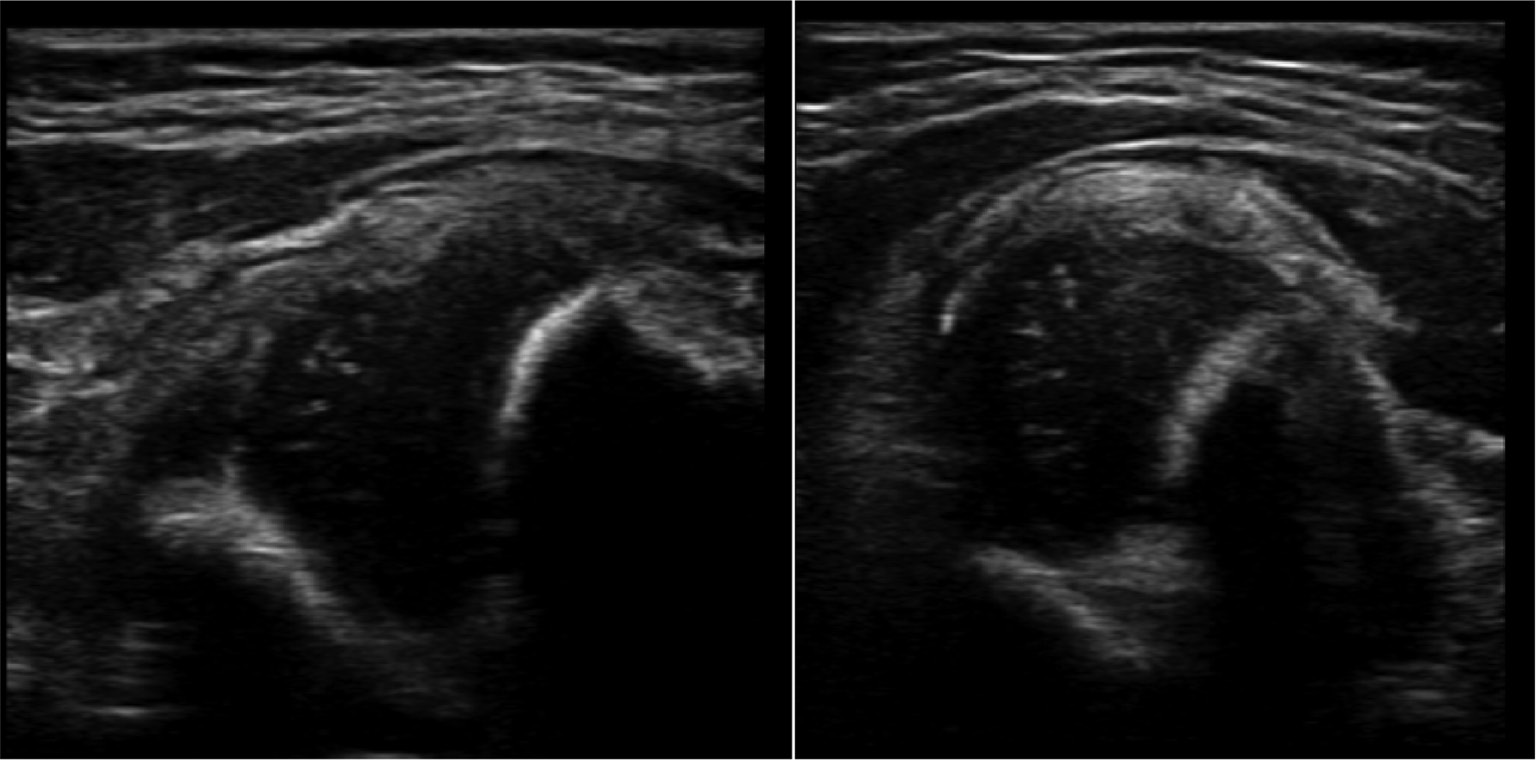

The simplified method keeps the patient on a regular exam table, avoiding the need for any specialized equipment. The examined hip is held at 90 degrees of flexion with slight adduction. The view in this plane is the so-called “transverse” image (Figure 4). The transducer is placed parallel to the long axis of the femur, and the position of the femoral head in relation to the acetabulum is determined. If the femoral head is in contact with the acetabulum, whether it may be dysplastic or not, that femoral head is located.

Figure 4. Schematic and overlay of a transverse image showing the position of the femoral head in relation to the acetabulum.

Step 2. Determine Whether the Hip is Stable or Unstable9

To assess stability under sonographic evaluation, the hip should be stressed by adducting and applying posteriorly directed force, simulating a Barlow test. Figure 5 demonstrates an unstable hip during the simulated Barlow test (Figure 5).

Figure 5. Unstable hip during simulated Barlow test.

Displacement of the femoral head can be measured during this maneuver by measuring the distance between two set points, typically the femoral head and the triradiate cartilage, before and after applying the stress. Displacement greater than 4 mm between the acetabulum and femoral head signifies instability.

Another option for determining stability is to look for the so-called “bird-in-flight” sign, a line drawn along the acetabulum and the proximal femoral metaphysis (Figure 6). This virtual line is akin to a Shenton line on a radiograph and should be contiguous. A broken line signifies an unstable hip.

Figure 6. Bird in flight sign.